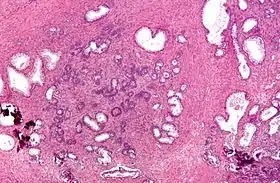

Micrograph of a transurethral resection of the prostate (TURP) specimen, showing BPH (nodular hyperplasia of the prostate) – left-of-center in image. H&E stain. | |